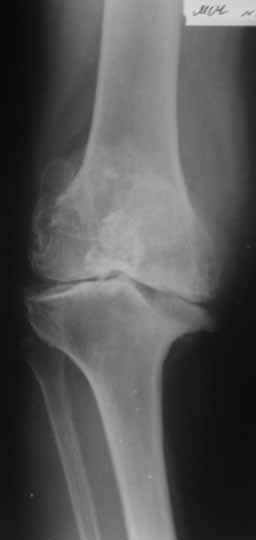

Пациентка 72 лет.Не обследовалась и не лечилась.

Работала поварихой до последнего времени.обратилась за медпомощью впервые.ходит без дополнительной опоры. Основные жалобы на ограничение движений и боли в правом коленном суставе.

Финансовые возможности ограничены.Чем можно помочь? Артродез? Протезирование?

Здравствуйте! А у вас нет ли R-гр? Для установления ст. артроза. Если же пациентка обращается первично, может стоит попробовать консервативное лечение?! НПВП, физиолечение, массаж, внутрисуставные блокады... Артродез и протезирование думаю всегда успеется.

однозначно протезирование

Больной несомненно показано эндопротезирование, однако случай не простой. Если у Вас нет достаточного опыта в проведении подобных операций, лучше направить больную в соответствующее лечебное

учреждение. По квоте.